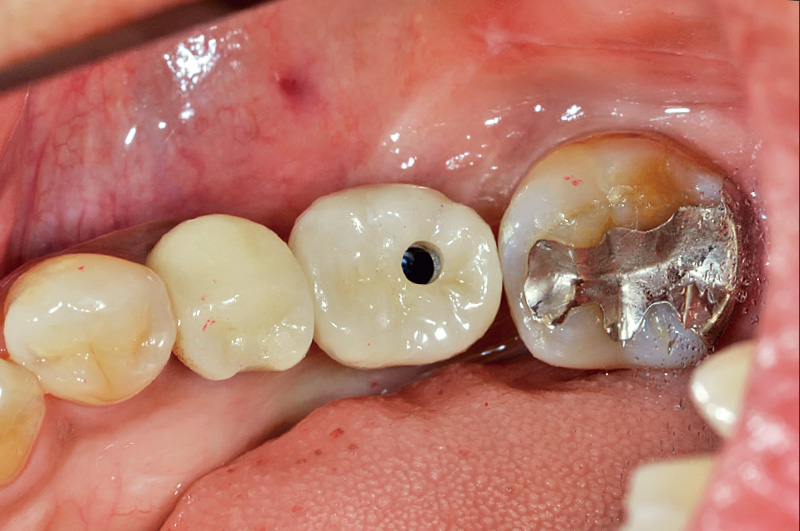

![[写真] 装着](/academic/dentalmagazine/wp-content/uploads/sites/2/2025/11/195-10_photo13.jpg)

図13 装着

今回二ケイ酸リチウムを使用し上部構造を作製することで、前方歯とも色調的に調和のとれた口腔内を再現可能としている。CERECをはじめとしたデジタル機器との相性の良さは、二ケイ酸リチウムやジルコニアなど高品位なマシナブルセラミック材料との相性の良さを示している。 -